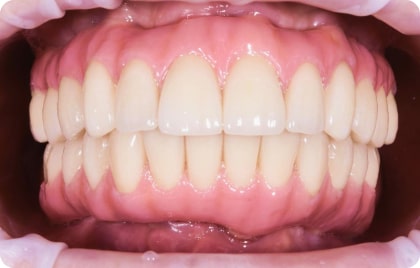

Зубы за 1 день от 7500₽ в месяц

с пожизненной гарантией

Установка

за 1 день